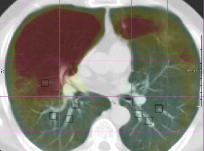

Muenzing et al. [2014] generated an uncertainty map by spatial interpolation of landmark-based quality estimates. On the contrary, our proposed system, which is trained on landmark locations, can be applied in all regions of the image. We showed this for two example images, see Fig. 5. It can be easily visualized that in the blue region, images are matched correctly. On the other hand, by tracking the vessels in the red region misalignment can be seen. Another note about the prediction is that there are no abrupt changes, and error varies smoothly from blue to yellow and then red, even though the error is predicted for each voxel independently.

Another example is given in Fig. 10(a-d). Although all landmarks indicate that the registration error is small in this slice, the quantitative results found several misregistered regions, which implies that few landmarks may not be sufficient to assess the registration quality of the whole image. In Fig. 10(e, f), it can be observed that the performance in the homogeneous area (left side of the images) is as good as the performance in the area with structure. The main reason of acceptable performance in the homogeneous area is that the training samples consist of landmarks as well as their neighborhood region, which can be homogeneous. Thus, the system is trained both for homogeneous regions and regions with structure.

Another example is given in Fig 10(g, h), where the proposed system is not able to predict the registration error correctly because of a shift in the slice direction.

Refer to caption

() Sample 1: IFsubscript𝐼𝐹{I}_{F}

(a) Sample 1: IM(𝐓b)subscript𝐼𝑀superscript𝐓b{I}_{M}(\bf{T^{\mathrm{b}}})

(b) Magnification of (a)

(c) Magnification of (b)

(d) Sample 2: IFsubscript𝐼𝐹{I}_{F}

(e) Sample 2: IM(𝐓b)subscript𝐼𝑀superscript𝐓b{I}_{M}(\bf{T^{\mathrm{b}}})

(f) Sample 3: IFsubscript𝐼𝐹{I}_{F}

(g) Sample 3: IM(𝐓b)subscript𝐼𝑀superscript𝐓b{I}_{M}(\bf{T^{\mathrm{b}}})

Figure 10: Several samples from the SPREAD dataset. The left column shows the fixed image with the ground truth registration error overlaid in color. The right column shows the moving image after registration with the registration error predicted by the proposed method overlaid in color.